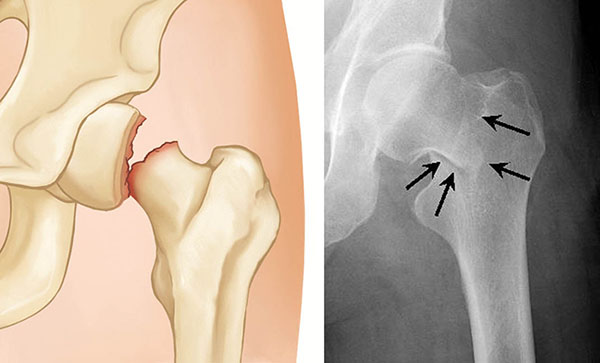

Geriatric Hip Fracture Treatment

Geriatric hip fractures are fractures in the upper-third of the thigh bone (femur) and/or around the hip joint sustained by elderly adults as a result of a fall.

A health care provider can often diagnose a hip fracture based on symptoms and the abnormal position of the hip and leg. An X-ray usually will confirm the fracture and show where the fracture is.

If your X-ray doesn't show a fracture but you still have hip pain, your provider might order an MRI or bone scan to look for a hairline fracture.